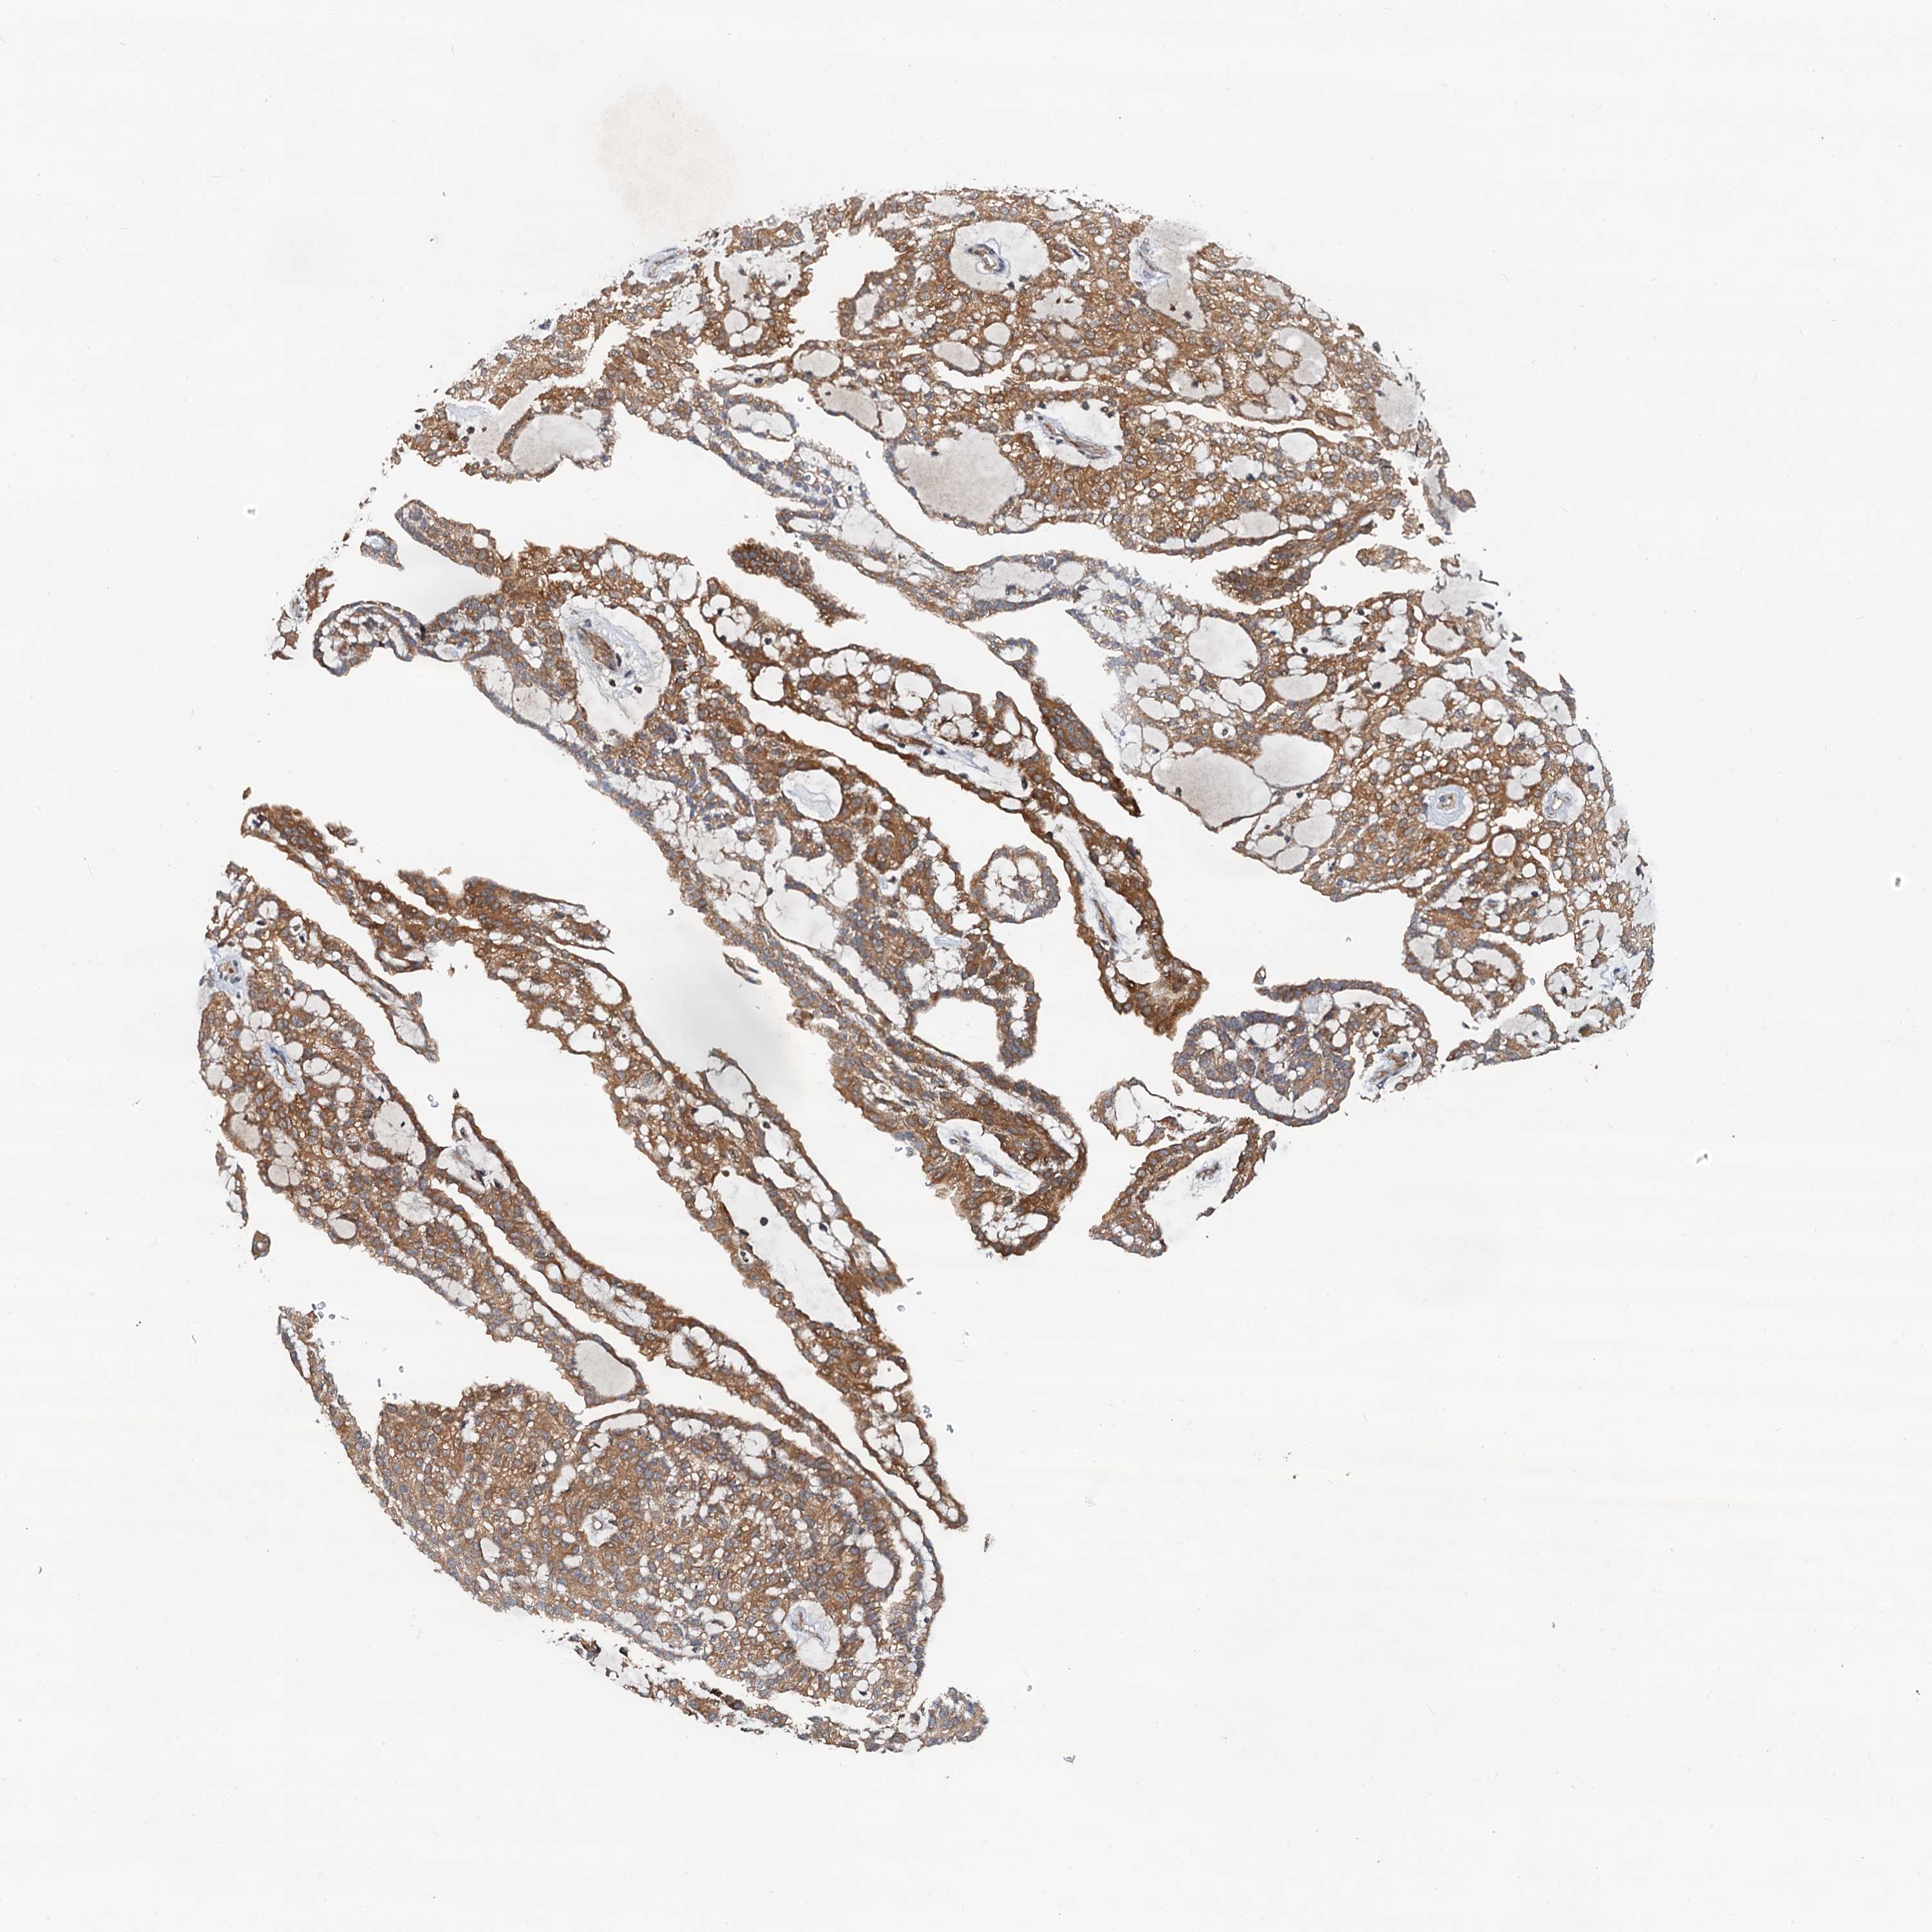

KIDNEY RENAL CLEAR CELL CARCINOMA (VALIDATION) - Interactive survival scatter ploti

The Survival Scatter plot shows the clinical status (i.e. dead or alive) for all individuals in the patient cohort, based on the same data that underlies the corresponding Kaplan-Meier plots. Patients that are alive at last time for follow-up are shown in blue and patients who have died during the study are shown in red.

The x-axis shows the expression levels (FPKM) of the investigated gene in the tumor tissue at the time of diagnosis. The y-axis shows the follow-up time after diagnosis (years). Both axes are complimented with kernel density curves demonstrating the data density over the axes. The top density plot shows the expression levels (FPKM) distribution among dead (red) and alive patients (blue). The right density plot shows the data density of the survived years of dead patients with high and low expression levels respectively, stratified using the cutoff indicated by the vertical dashed line through the Survival Scatter plot. This cutoff is automatically defined based on the FPKM cutoff that minimizes the p-score. The cutoff can be changed by dragging the vertical line or by entering a cutoff value in the square labeled "Current cut-off".

Under the Survival Scatter plot the p-score landscape (black curve; left axis) is shown together with dead median separation (red curve; right axis). Dead median separation is the difference in median mRNA expression between patients who have died with high and low expression, respectively. It is calculated as follows: median FPKM expression of dead patients with high expression - median FPKM expression of dead patients with low expression. This is intended to aid the user in visually exploring custom cutoffs and the associated p-scores and dead median separation.

Individual patient data is displayed and can be filtered by clicking on one or more of the category buttons on the top of the page. Categories describing expression level and patient information include: high, low, alive, dead, female, male and tumor stages. The scale of the x-axis can be toggled between linear and log-scale by clicking on the "x log" button. Mouse-over function shows TCGA ID, patient information and mRNA expression (FPKM) for each patient.

& Survival analysisi

Kaplan-Meier plots summarize results from analysis of correlation between mRNA expression level and patient survival. Patients were divided based on level of expression into one of the two groups "low" (under cut off) or "high" (over cut off). X-axis shows time for survival (years) and y-axis shows the probability of survival, where 1.0 corresponds to 100 percent.

AAGAB is not prognostic in Kidney Renal Clear Cell Carcinoma (validation)

Best expression cut offi

: 14.22

P scorei

N/A

TCGA RNA samplesi

RNA-seq data is reported as average FPKM (number Fragments Per Kilobase of exon per Million reads), generated by the The Cancer Genome Atlas (TCGA) .

Normal distribution across the dataset is visualized with box plots, shown as median and 25th and 75th percentiles. Points are displayed as outliers if they are above or below 1.5 times the interquartile range. FPKM values of the individual samples are presented next to the box plot.

Average pTPM 19.7

Number of samples 100